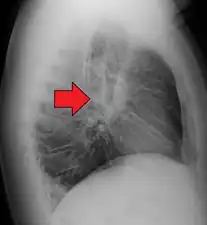

Hilar adenopathy especially on the person's left (AP CXR)

Hilar adenopathy especially on the person's left (lateral CXR)